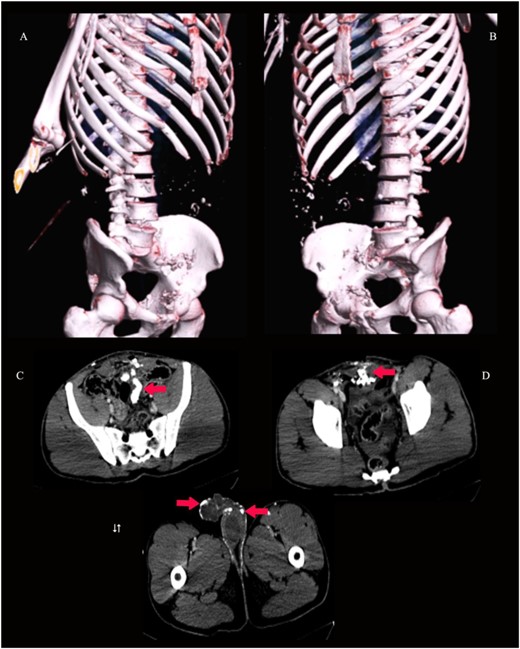

3D virtual reconstruction images (A and B) and axial CT pelvis (C, D and E) show innumerable radio-opaque foreign bodies (shrapnel) in the peritoneal cavity, anterior rectus abdominis muscle and the subcutaneous tissue of the penis, scrotum and left thigh, as shown by arrows.